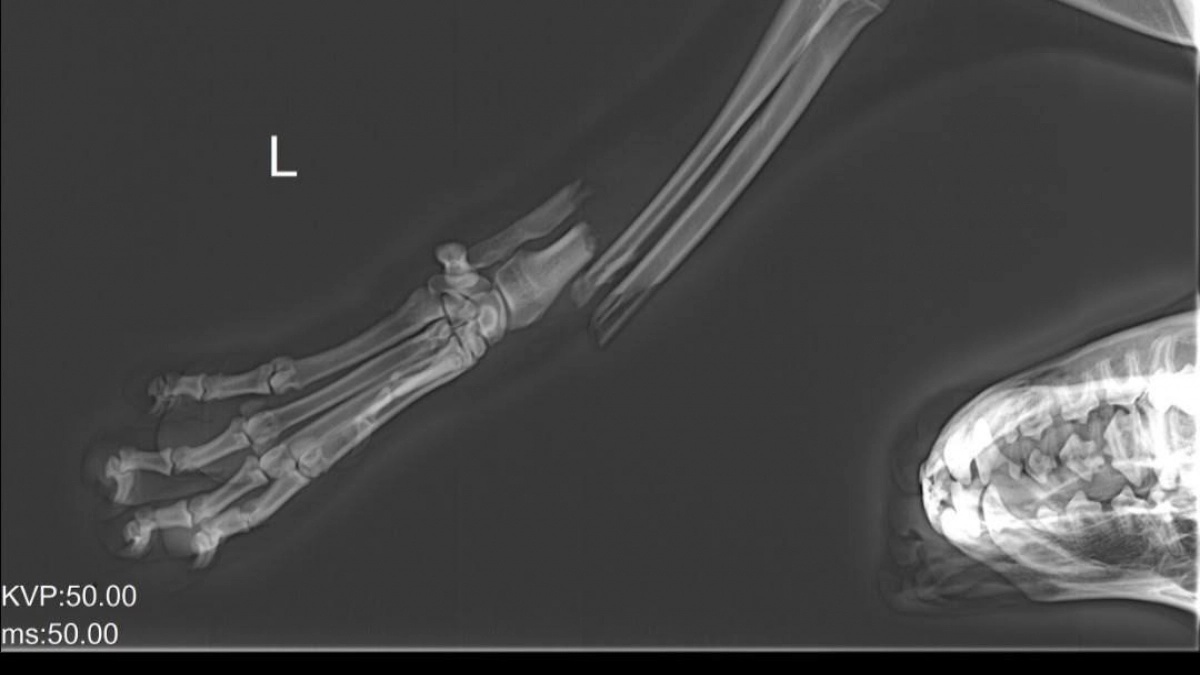

Пёс по кличке Бадди оказался в беде после того, как его сбила машина. По словам очевидцев, таксист переехал собаке переднюю лапу и уехал, даже не остановившись.

Травма была очень серьёзной. Кость буквально торчала наружу, рана кровоточила. Люди, ставшие свидетелями случившегося, не остались равнодушными и отнесли пса домой к хозяйке. Однако дальше ситуация стала ещё тяжелее.

Хозяйка не смогла отвести животное к ветеринарам. Вместо этого она попыталась помочь самостоятельно: зафиксировала повреждённую лапу с помощью палки и обмотала бинтом. Но этого оказалось недостаточно. Бадди оставался без профессиональной помощи, без обезболивания и должного ухода целых четыре дня.